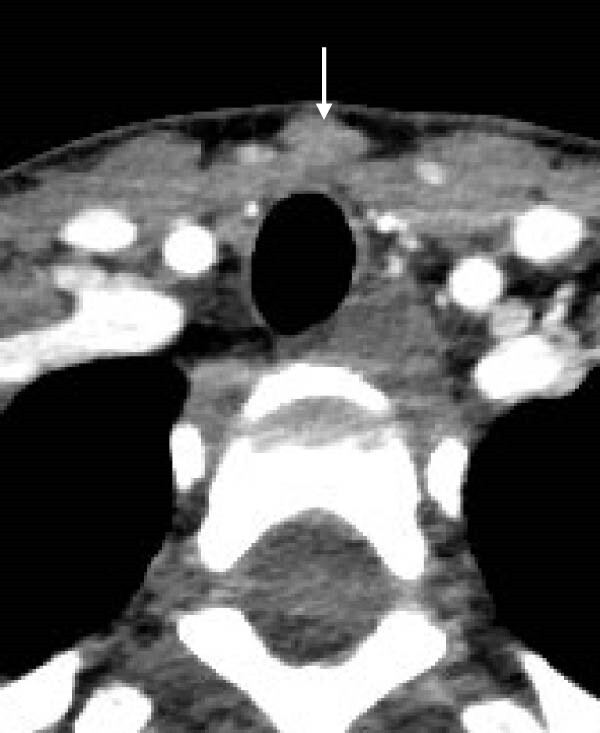

В то же время, во время сцинтиграфии паращитовидных желез с 99мТс-МИБИ не было отмечено накопления препарата. Далее была проведена четырехмерная компьютерная томография (4D КТ), которая не показала наличия глубоких узлов в средостении (рис. 8-11)). По результатам обследования был исключен синдром множественной эндокринной неоплазии (МЭН), хотя семья отказалась от генетического тестирования.

Рисунки 8-11. Снимки 4D КТ в поперечной (8,9), сагиттальной (10) и коронарной (11) плоскостях, где заметны слегка контрастируемые узелки в претрахеальной подкожной клетчатке (8-10) и в нижнем полюсе левой доли щитовидной железы (11). Размеры варьируют от 3 до 12 мм.